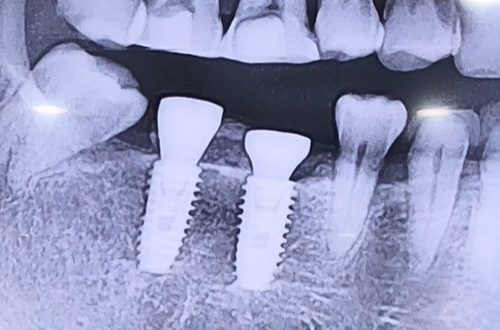

AFTER

발치한지 오래된 오른쪽 아래 어금니 두 개를

회복시키기 위한 임플란트를 위해 내원하신 환자분이십니다.